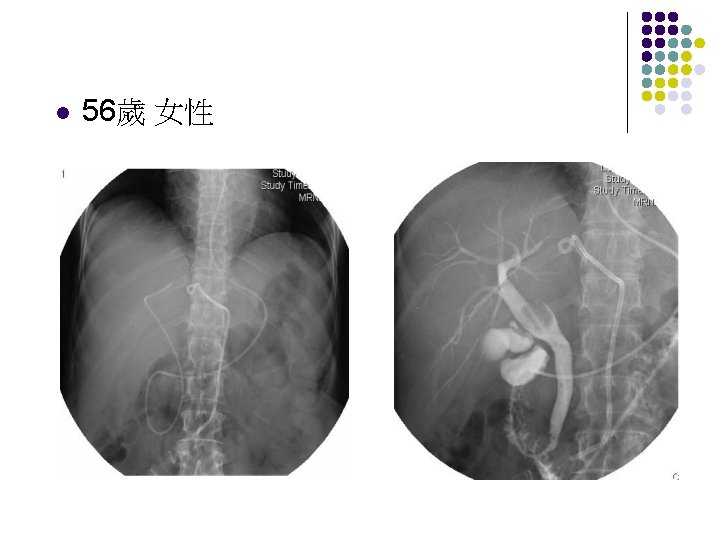

l 79歲 女性 PTGBD